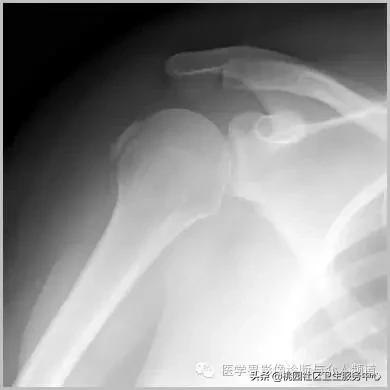

六、肌腱钙化/滑囊炎并钙化

肩关节最常见:肱二头肌长头、肩峰下滑囊钙化,可伴有急性疼痛、肿胀,局部压痛。

肱二头肌肌腱钙化(肩周炎)

肩周炎